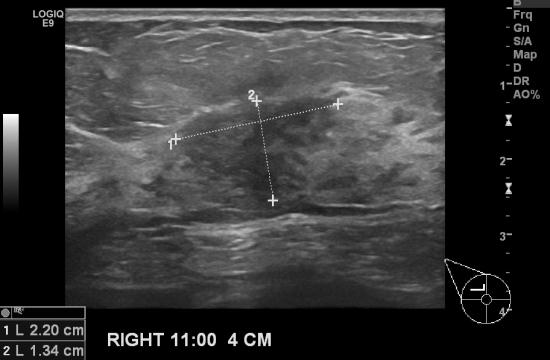

두달전부터 우측 유방에 몽우리가 만져지면서 없어지지 않고 당기는 증상때문에 내원하신

51세 여성분입니다.

유방초음파와 조직검사를 통해 우측 유방암 2.2cm, 침윤성 유방암이 진단되었고

다행히 우측 겨드랑이에는 전이된 림프절 소견이 없어보이셨습니다.